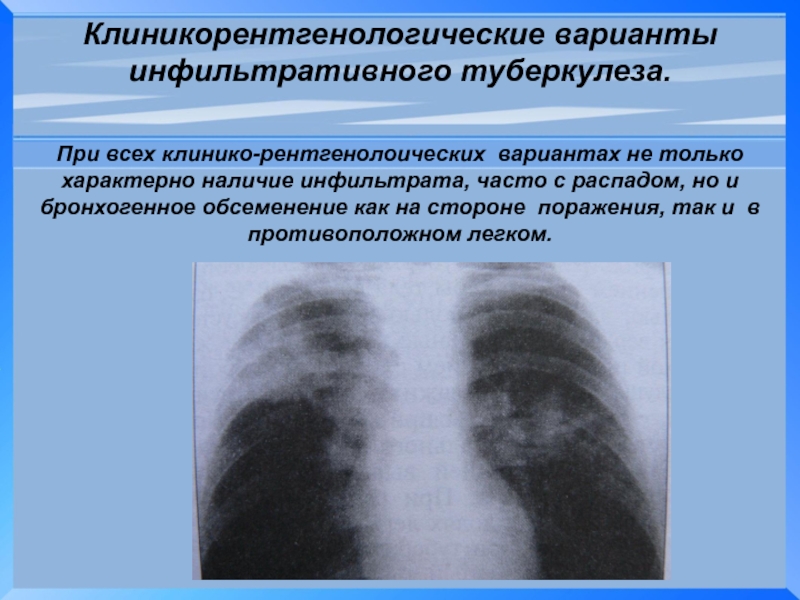

Очаговый и инфильтративный туберкулез презентация - 94 фото